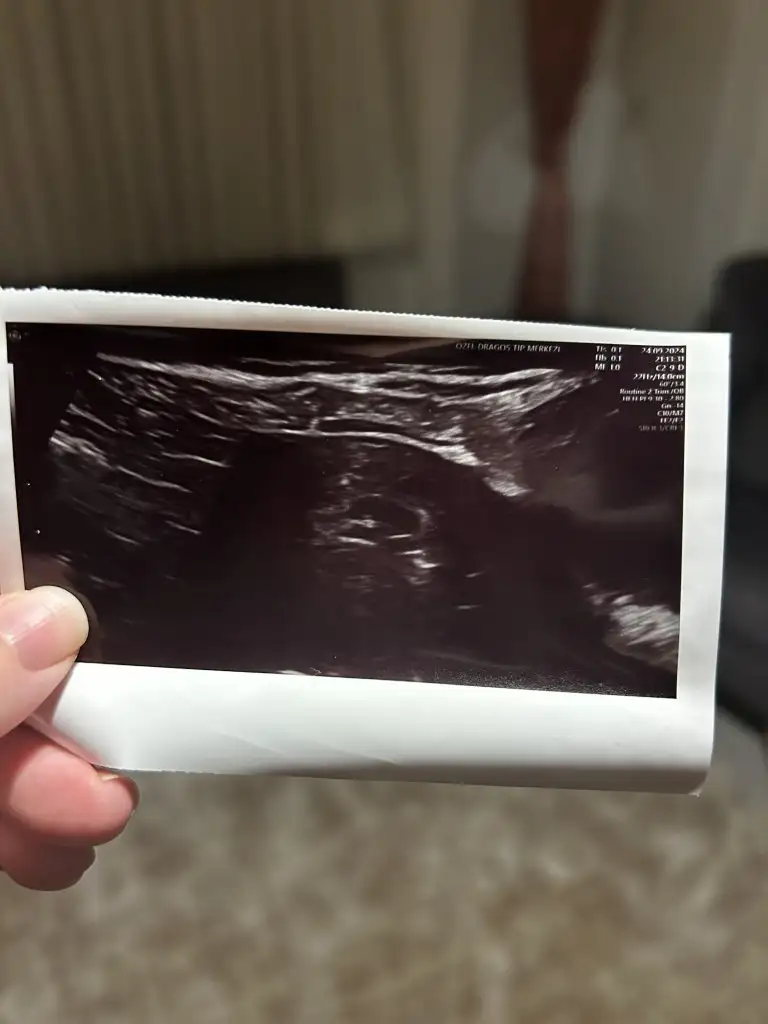

Bizde 6 haftalık olduk inşallah haftaya kalp atışını duyarız. Dün gece çok korkuttu bizi ama iyiyiz şükür 🙏🏼